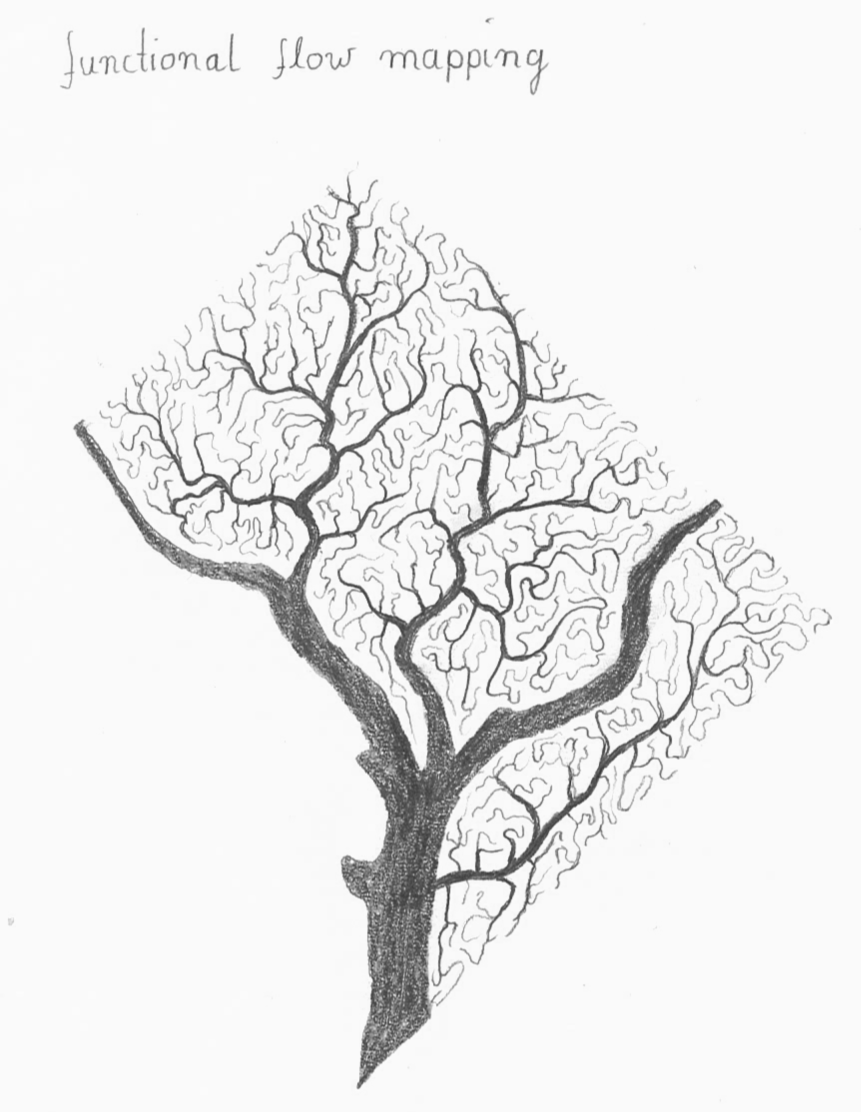

In the early days of the Internet, modems (modulator-demodulator) were used to (i) convert digital information into audio streams, (ii) transfer them across telephone lines, and (iii) convert them back into the digital domain. Here, we aim to do the same thing with pixel data of MRI scans. However, instead of audio signal we will use machine-readable visual information: QR codes.